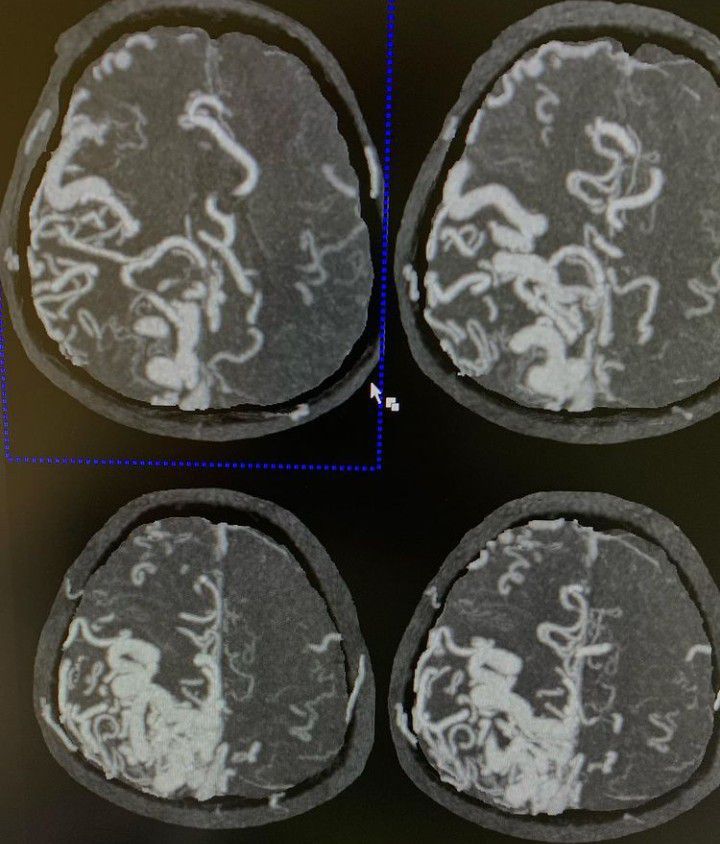

Brain arteriovenous malformations are type of intracranial high-flow vascular malformation composed of enlarged feeding arteries, a nidus of vessels closely associated with the brain parenchyma through which arteriovenous shunting occurs, and draining veins.